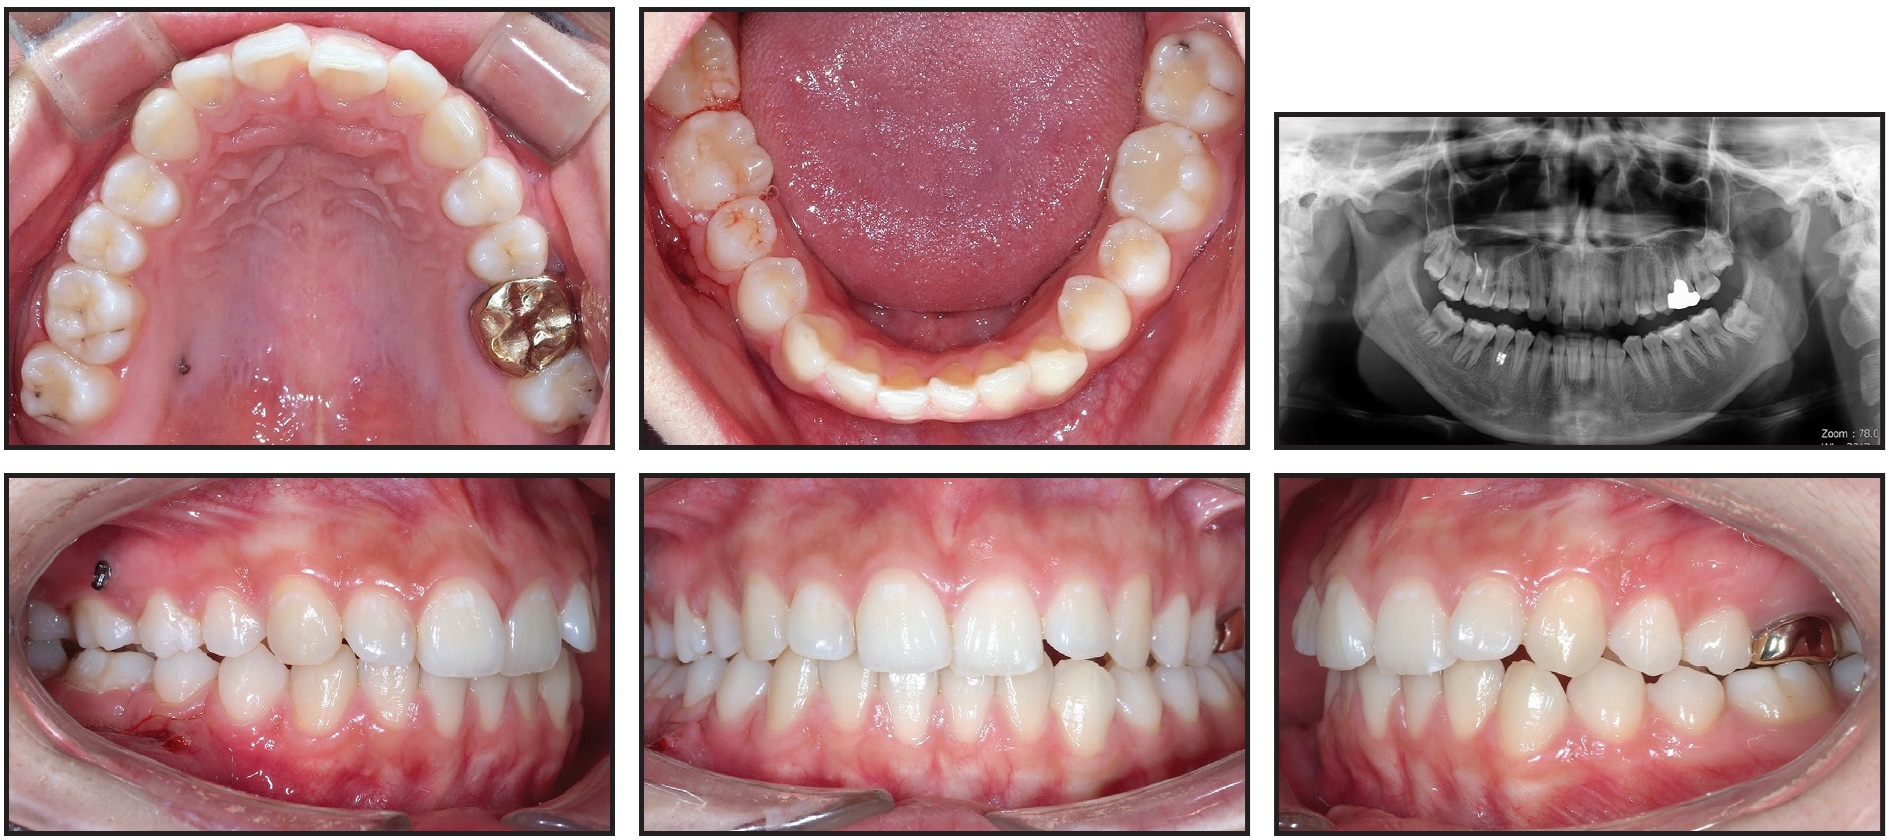

A 16-year-old female scheduled for prosthodontic treatment was referred for intrusion of an overerupted upper right first molar after decay of the lower first molar (Fig. 6).

Fig. 6 Case 2. 16-year-old female patient with extracted lower right first molar and extruded upper right first molar before treatment.

The patient presented with the lower right molar already extracted, so intrusion of the upper right first molar and protraction of the lower right second and third molars were planned.

Two small-headed micro-implants were placed in the buccal (7mm) and palatal (10mm) sides of the upper right posterior area, and an intrusion force was applied to the upper right first molar (Fig. 7).

Fig. 7 Case 2. A. 7mm micro-implant placed in upper right posterior bone on buccal side and 10mm micro-implant on palatal side. B. Intrusion force applied to upper right first molar.

After a modest amount of intrusion had been achieved, protraction of the lower second and third molars was started to close the extraction space with micro-implant anchorage.

After six weeks of treatment, two small-headed 6mm micro-implants were placed into the buccal alveolar bone between the lower right first and second premolars, tied with a stainless steel ligature wire, and built up with composite resin, as in Case 1 (Fig. 8). A standard .018" upper-incisor bracket was bonded to the composite, a tube was bonded to the lower second molar, and an .017" × .025" TMA sectional wire was inserted. Reactivation was performed by tightening the ligature wire every four weeks (Fig. 9).

Fig. 8 Case 2. A. Bracket bonded over two micro-implants between lower right first and second premolars, as in Case 1. B. Mesial force applied with TMA sectional wire.

Fig. 9 Case 2. Mesial tipping of lower right second molar and development of bone atrophy near first-molar extraction space during protraction. A. After six months of treatment. B. After 10 months of treatment. C. After 14 months of treatment.

The intrusion force was applied continuously to the upper right first molar, and the lower second molar was intruded slightly by the sectional archwire to avoid occlusal contact during protraction. Panoramic radiographs indicated forward tipping of the lower second molar rather than bodily movement.

After 20 months of treatment, most of the lower right first-molar space had been closed by the mesial movement of the second molar. A gingival cleft had developed as a result of soft-tissue folding, and bone loss on the mesial side of the lower right second molar was evident on a panoramic radiograph at 24 months (Fig. 10).

Fig. 10 Case 2. A. Gingival cleft caused by soft-tissue folding after 24 months of treatment, with bone loss apparent on mesial side of lower right second molar. B. Gingival cleft evident in interproximal area of second premolar and protracted second molar. C. Illustration of gingival cleft caused by closure of edentulous space.

Total treatment time was 27 months (Fig. 11). The post-treatment records showed the gingival cleft between the second premolar and the protracted second molar, bone resorption in the mesial part of the second molar, and apical root resorption of the protracted second molar. In addition, bone atrophy in the buccolingual dimension was observed in the bone between the second premolar and the second molar.

Fig. 11 Case 2. Patient after 27 months of treatment.